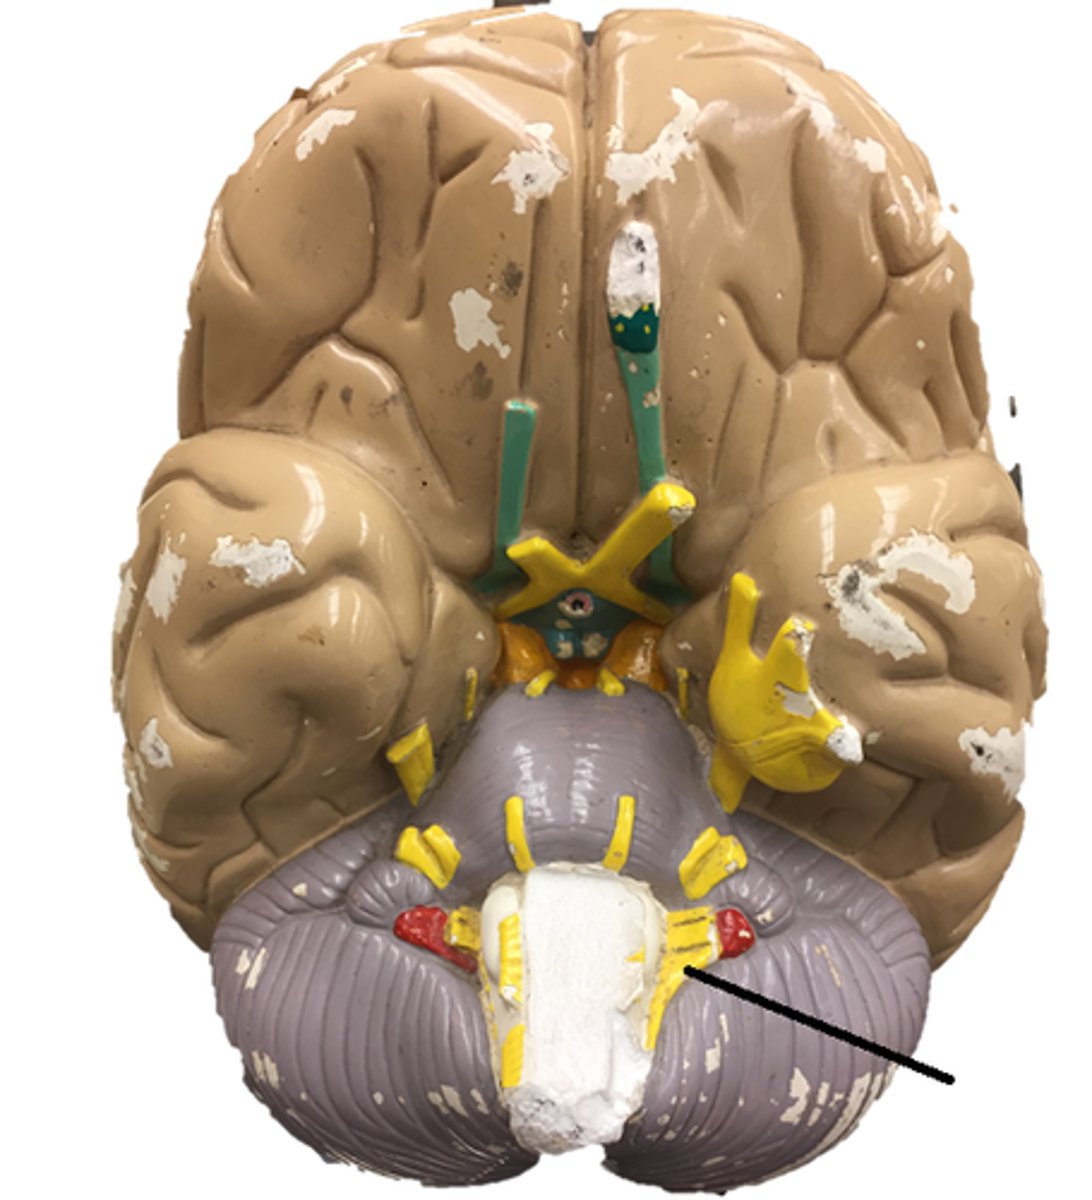

Cerebellum

anterior lobe of cerebellum

posterior lobe of cerebellum

vermis

cerebellar peduncles

arbor vitae

Primary fissure